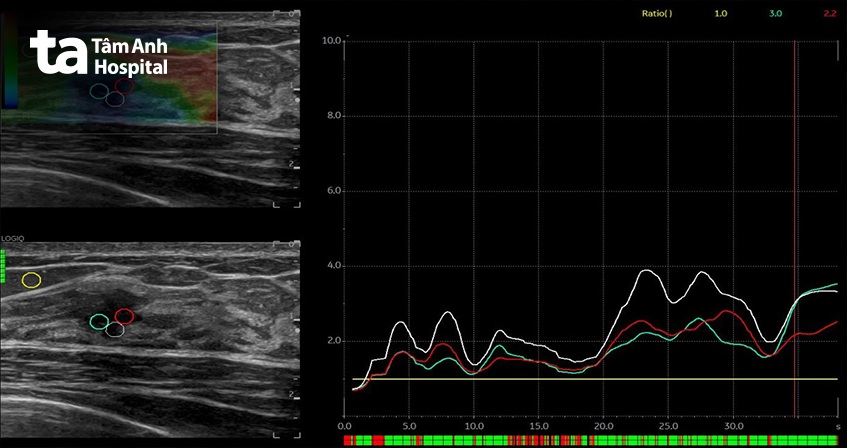

Kết quả siêu âm cho thấy khu vực sang thương ở vú phải của chị có hình thái không đều, bờ tạo gai, tăng sinh mạch máu ngoằn ngoèo, đồng thời cứng trên siêu âm đàn hồi. Để chị H. dễ hiểu về siêu âm đàn hồi, bác sĩ CKI Phạm Tấn Phát, Trung tâm Chẩn đoán hình ảnh & Điện quang can thiệp, giải thích máy siêu âm GE E10S có thể đánh giá mức độ đàn hồi của sang thương thông qua màu sắc.

Nếu khối u hiển thị màu xanh dương là cứng, còn màu xanh lá là trung tính, riêng màu vàng và đỏ là mềm. Và trường hợp của chị thì máy cho thấy vùng có màu xanh dương (cứng) bao trọn sang thương.

Với những tiến bộ của khoa học kỹ thuật, các máy siêu âm thế hệ mới hiện nay có thể giúp phát hiện những sang thương rất nhỏ, trên dưới 5mm. Ngoài hình ảnh thường quy trên siêu âm trắng đen, tín hiệu và cách phân bố mạch máu trên siêu âm doppler màu, cũng như đánh giá độ cứng trên siêu âm đàn hồi, cung cấp nhiều thông tin hơn giúp các bác sĩ siêu âm có thể đưa ra chẩn đoán chính xác hơn.

Sự kết hợp từ nhiều thông tin dữ liệu giúp nâng mức độ nghi ngờ của sang thương lên BIRADS 4B (10 – 50% nguy cơ ác tính), giúp bác sĩ có cơ sở chỉ định sinh thiết nhằm khẳng định khả năng lành – ác tính của sang thương.

Bác sĩ CKI Phạm Tấn Phát chia sẻ thêm máy siêu âm GE E10S là một trong những dòng máy tiên tiến nhất về siêu âm vú, có độ phân giải hình ảnh cao, đầu dò kích thước lớn cùng với nhiều tính năng phụ trợ như siêu âm đàn hồi, siêu âm vi mạch… giúp hỗ trợ tốt hơn trong đánh giá và phân loại mức độ nghi ngờ của các bất thường ở vú.